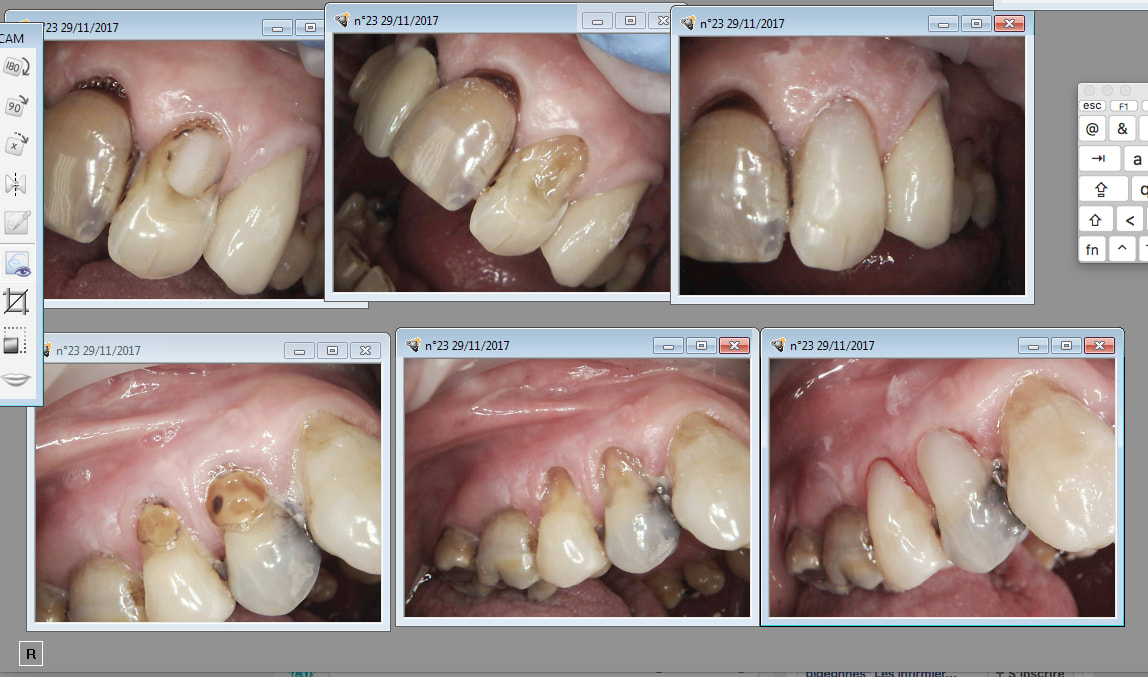

Regardez moi voir ce que j’ ai trouvé au fond d’une armoire :)))